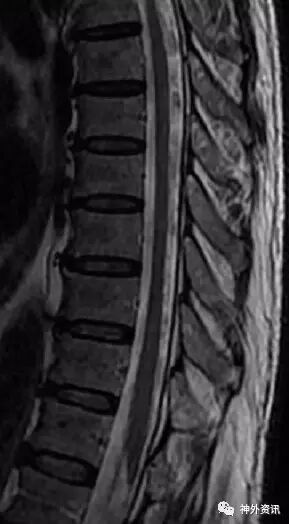

术后2天复查CTA见腰椎管内术前扩张的血管不显影(图5)。术后3个月患者复查MRI见脊髓背侧扩张的血管消失,脊髓水肿缓解(图6)。患者双下肢肌力及大小便功能恢复正常。

图5. 术后CTA显示左侧腰4/5稍扩大的椎板间小骨窗。椎管内术前扩张的血管不显影。

图6. 术后3个月复查脊髓MRI见脊髓背侧扩张的血管消失,脊髓水肿缓解。